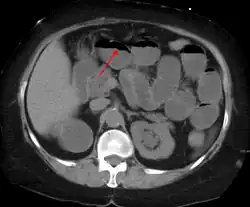

A small bowel obstruction as seen on CT

Small bowel dilation on CT scan in adults[14]

Diameter Assessment

<2.5 cm Non-dilated

2.5-2.9 cm Mildly dilated

3-4 cm Moderately dilated

>4 cm Severely dilated